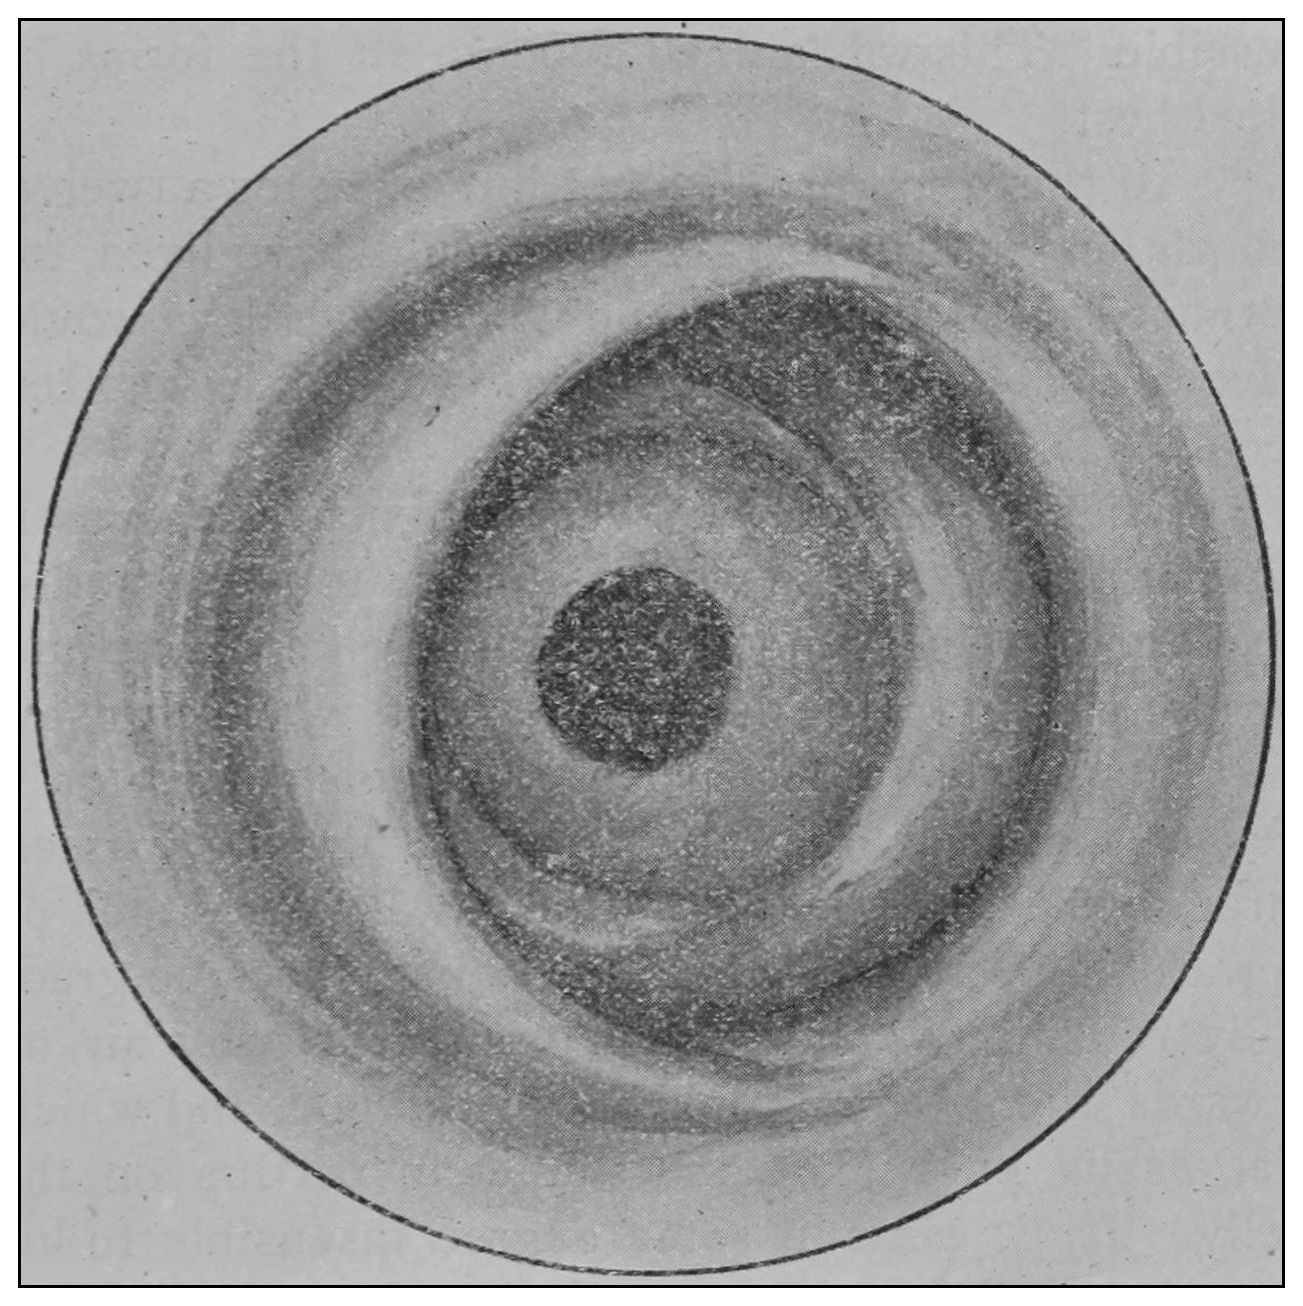

Hyrtl employed atmospheric distention after removal of the gut, and observed an appreciable thickening of the wall of the rectum beneath the mucous membrane, and with apparent reason assumed this thickening to be muscle only. Under the same manipulations a valve may be made to lose its valvular form and seem to support this view.

The photographic reproductions here published are documentary evidence of the existence of the obstructions under discussion. The sketch, Fig. 33, which was drawn from the valve while under the microscopic lens, exhibits the character of these obstructions and proves it that of a typic anatomic valve, and the absence of permanent bands of any other character in this organ is evidence that the semilunar valves and the so-called plica transversalis recti, Falten des Rectums, sphincter ani tertius, superior sphincter, and detrusor fecium muscles are one and the same thing and this thing is essentially a valve. It is most prominent when the gut is most distended.